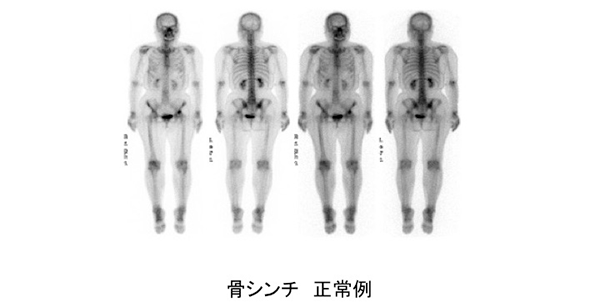

全身骨シンチグラフィ 乳癌 肺癌 前立腺癌等の骨転移病巣の検出

主な核医学検査 骨 骨シンチグラフィ 核医学検査のご案内 医療関係者

骨シンチグラフィーとは 佐賀大学病院放射線科アンオフィシャル

全身骨シンチグラフィ 乳癌 肺癌 前立腺癌等の骨転移病巣の検出

骨シンチグラフィによる骨転移の診断 Bone Scan Ct Mri画像診断